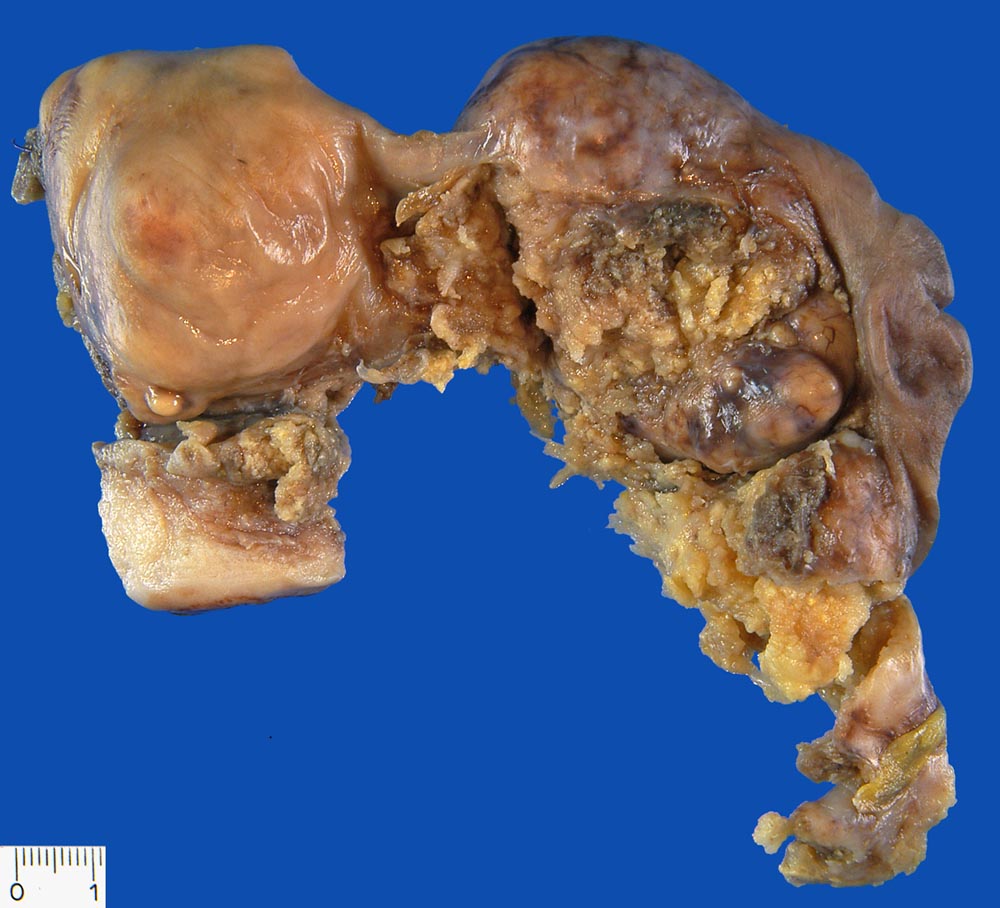

PathoPic ID 9558 - Serös papilläres Ovarialkarzinom

Serös papilläres Ovarialkarzinom

maligner Tumor

Ovar

Uterus mit rechter Adnexe. Papillärer Tumor ausgehend vom rechten Ovar. Ausgedehnte Tumorinfiltration der Serosaoberfläche.

Serös papilläres Karzinom

Karzinom im kleinen Becken

Makroskopie